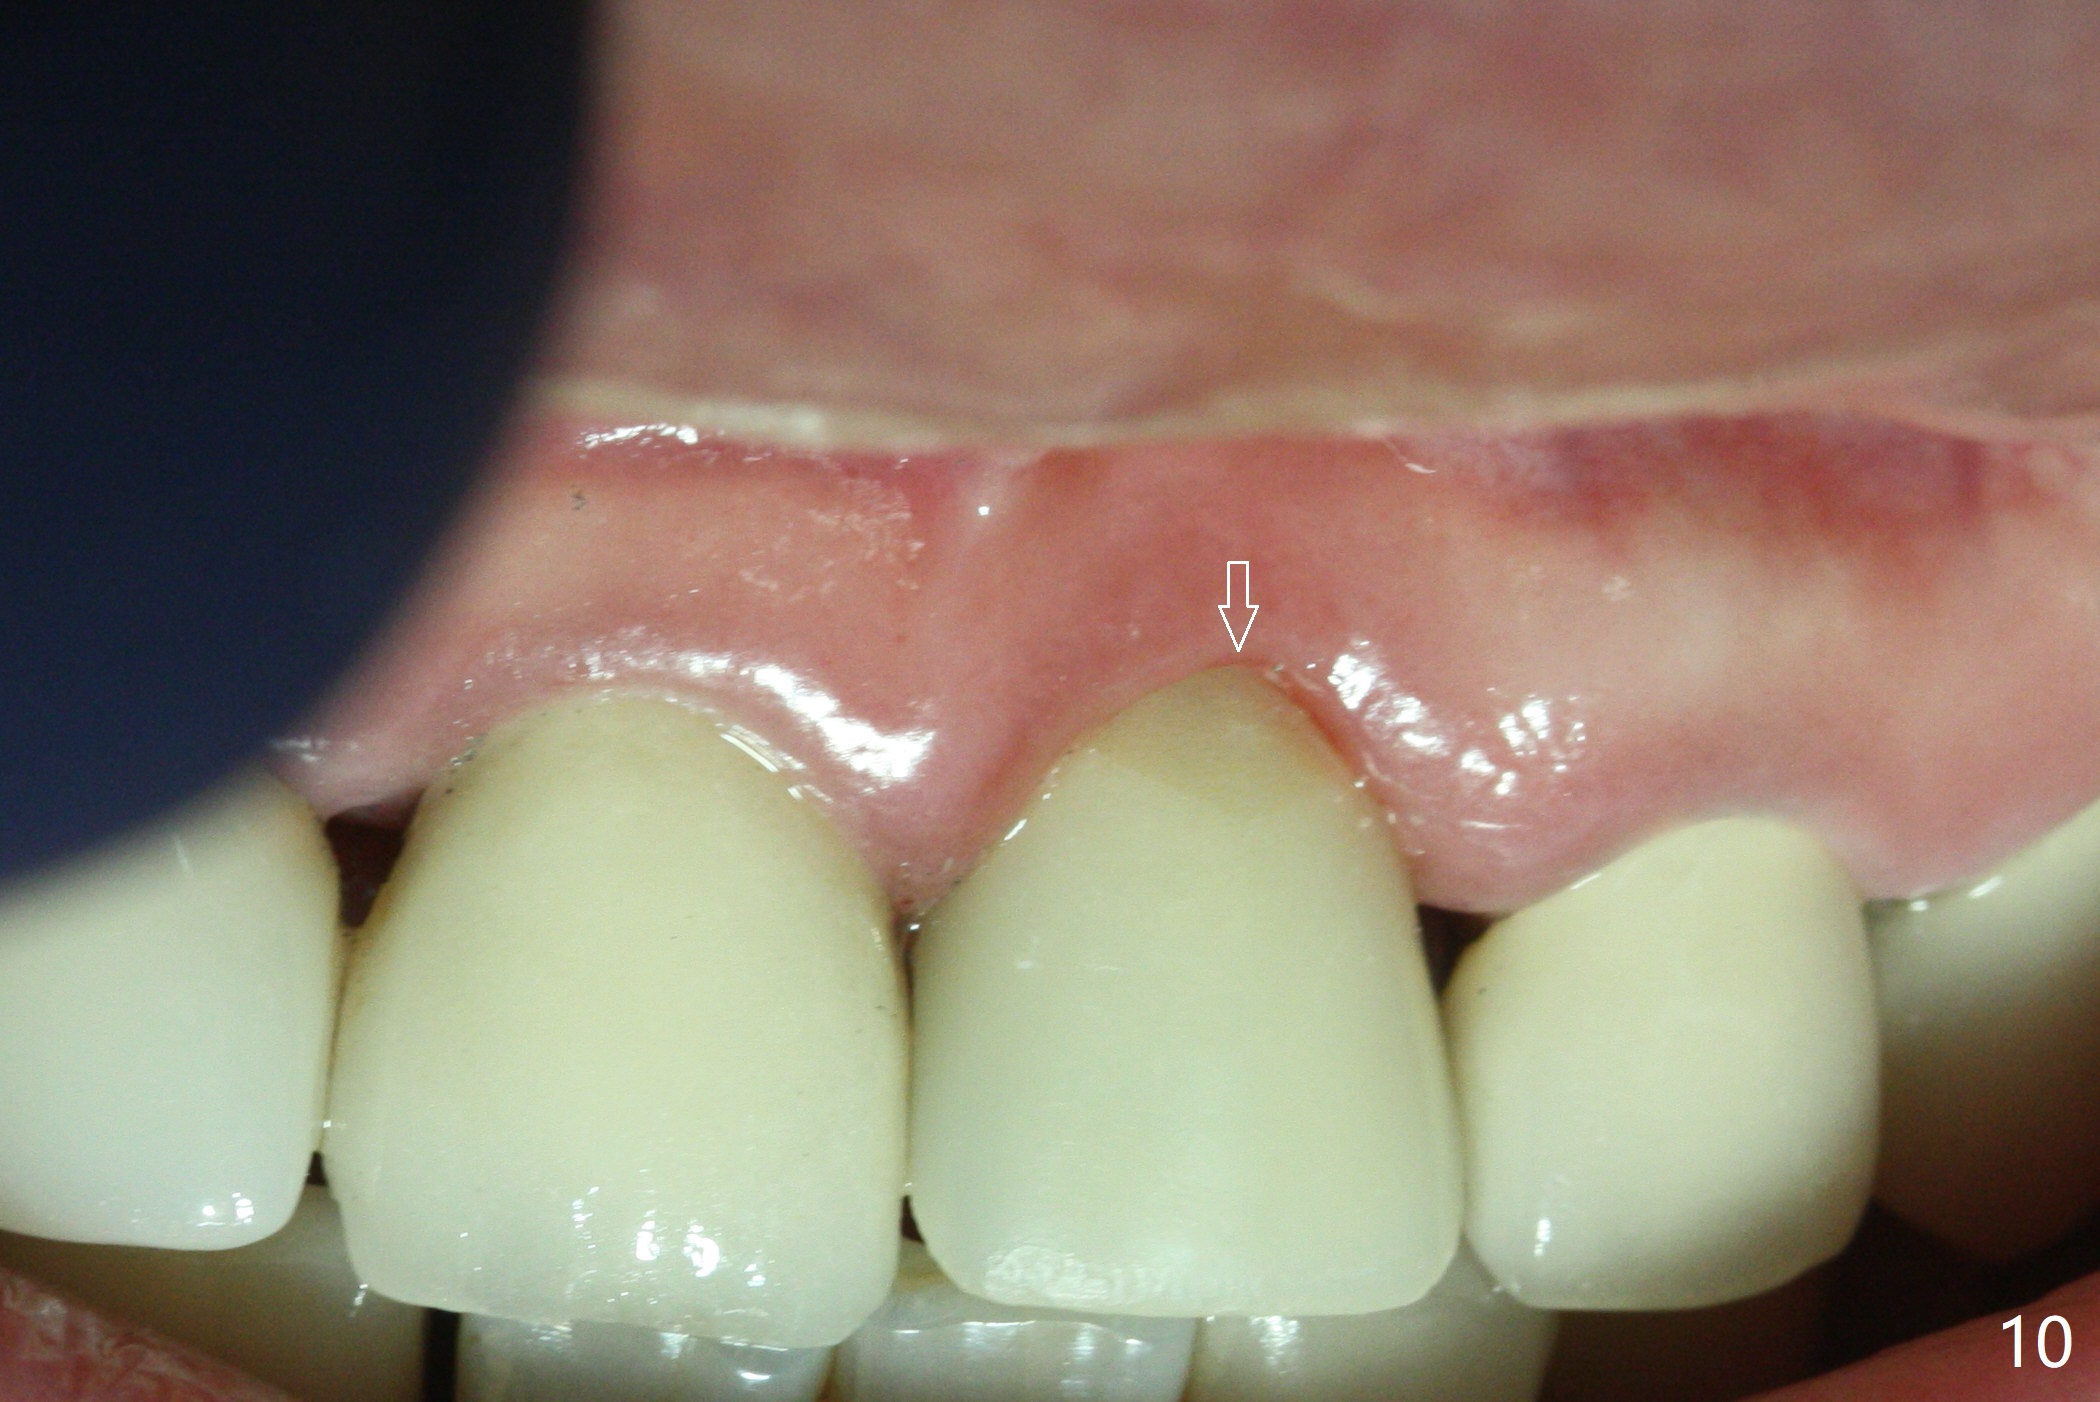

Nasal Floor

The buccal contour at #9 seems to be slightly concave preop (Fig.1,2 (*)). In fact the buccal plate is found to be lost when the tooth is extracted. Osteotomy is initiated as palatal as possible apical, but the occlusion dictates the coronal end of the osteotomy should be buccal, leaving the buccal gap ~ 2 mm for bone graft. The initial osteotomy (18 mm deep) appears to be close to the Incisive Foramen (Fig.3 blue dashed line). The nasal floor appears to be intact when the drill is removed. Subsequent osteotomy is adjusted so that the apical end of the osteotomy moves distal; when a 3.8x15 mm dummy implant is partially placed, there is clearance (Fig.4). It remains so when a definitive implant is seated (Fig.5); Vanilla graft is placed (Fig.5 *) before placement of a 4.5x5.5(3) mm abutment. More allograft is placed when an immediate provisional is fabricated (Fig.6 arrow and *). The gingiva remains to be recessive 1 month postop (Fig.7). It seems to be related to the bulky gingival margin of the provisional (Fig.8 *). After trimming the latter (Fig.9 *), the gingival margin immediately returns close to normal (Fig.10). The gingival margin is even between #8 and 9 two months postop, but the bone graft is exposed apically (Fig.11 ^). It may heals by itself. Otherwise debridement, regraft, PRF and suture are pending. The coronal portion of the socket heals 4 months postop (Fig.12). The gingival cuff forms by the immediate provisional (which is removed for impression) 4 months postop (Fig.13 *). While the full Zirconia crown at #7 remains intact (Fig.14), the PFM at #9 has porcelain chip (Fig.15). It is partially due to the occlusion; while the crown at #7 has clearance with the opposing dentition (Fig.16 *), the one at #9 has no. The access hole at #9 (Fig.17 *) seems to weaken the crown structure. There is no access hole at #7. No solid posterior support is another contributing factor for chip (Fig.18). The buccal plate has mild atrophy at #7 and 9 (Fig.19 *). A piece of bone graft is being expelled apically at #9 (Fig.20 >) and is removed subsequently (Fig.21). Before impression for repacking porcelain, the opposing incisal edge has been shortened (Fig.22 arrows, as compared to Fig.16). Since the ideal access hole is at the incisal edge (Fig.25 black circle), buccal to the existing one (Fig.24 A), the abutment is torqued before the repaired crown is recemented (Fig.23). Finally the crown has occlusal clearance (Fig.26). Porcelain chips again around the access hole of PFM 1.5 years post 2nd cementation. The dense bone at the crest (*) cannot explain why the abutment is not loose, since it remains incompletely seated (>). As it was trimmed short, an angled abutment is used (Fig.28). The coronal end is lingual, while #9/24 is edge to edge. The lingual aspect of the coronal end of the abutment is heavily trimmed to reduce bulkiness. To prevent chip, Zirconium crown will be fabricated in spite of the fact that it does not match the PFM of #8 (potential shade discrepancy). The patient is pleased with the new Zirconia crown (Fig.29).